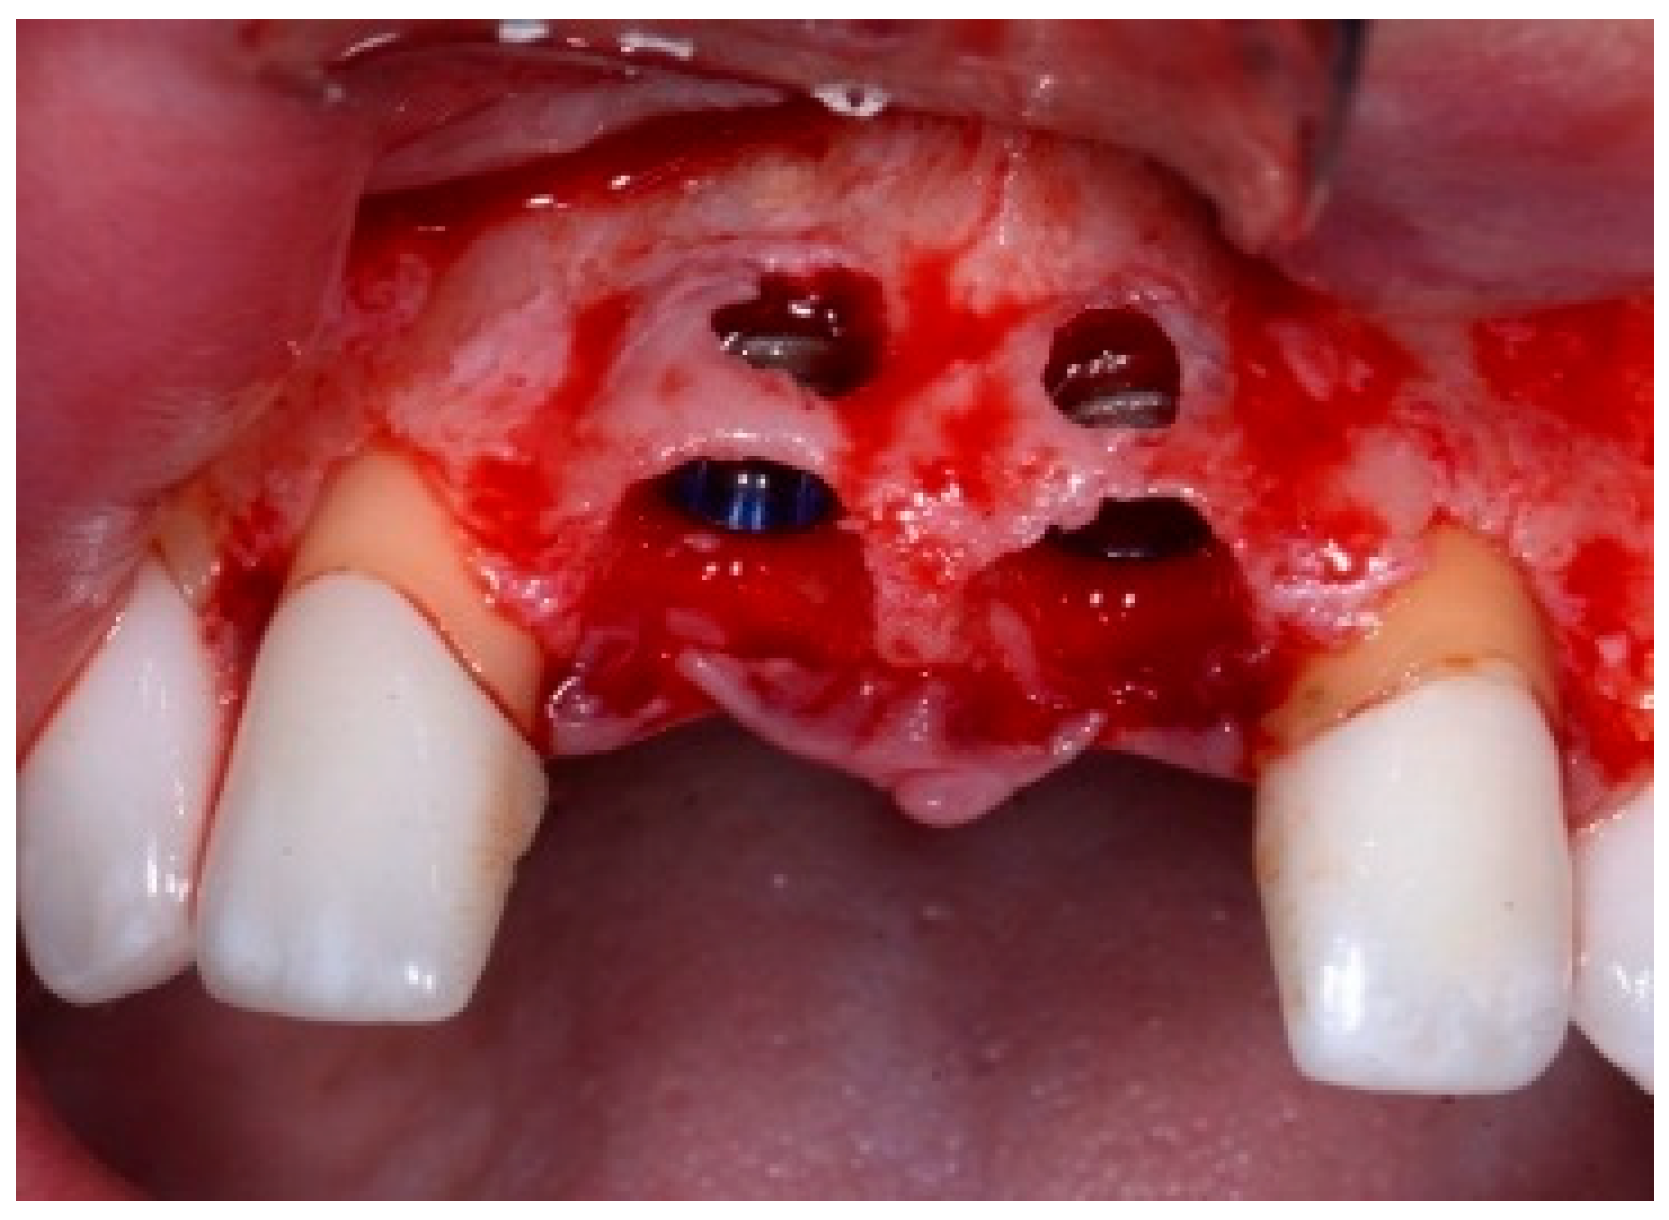

One hour before the surgical procedure, the patient received a prophylactic dose of 1 g of amoxicillin. Following local anesthesia, surgical access was obtained by raising a full-thickness aesthetic flap extending to the distal line angles of the lateral incisors. The full-thickness flap was extended 3–5 mm beyond the apical margin of the defect. The two central incisor roots were extracted, and the sockets were curetted with surgical curettes to remove all the granulation tissue (Figure 2). The sockets were assessed for the presence of a dehiscence and or fenestration. Two implants (Adin Dental Implants, Englewood, NJ, 07632, USA) were placed according to the manufacturer’s instructions (Figure 3).

Figure 2.

Clinical view immediately after extraction.

Figure 3.

Clinical view of the placement of two maxillary anterior implants.